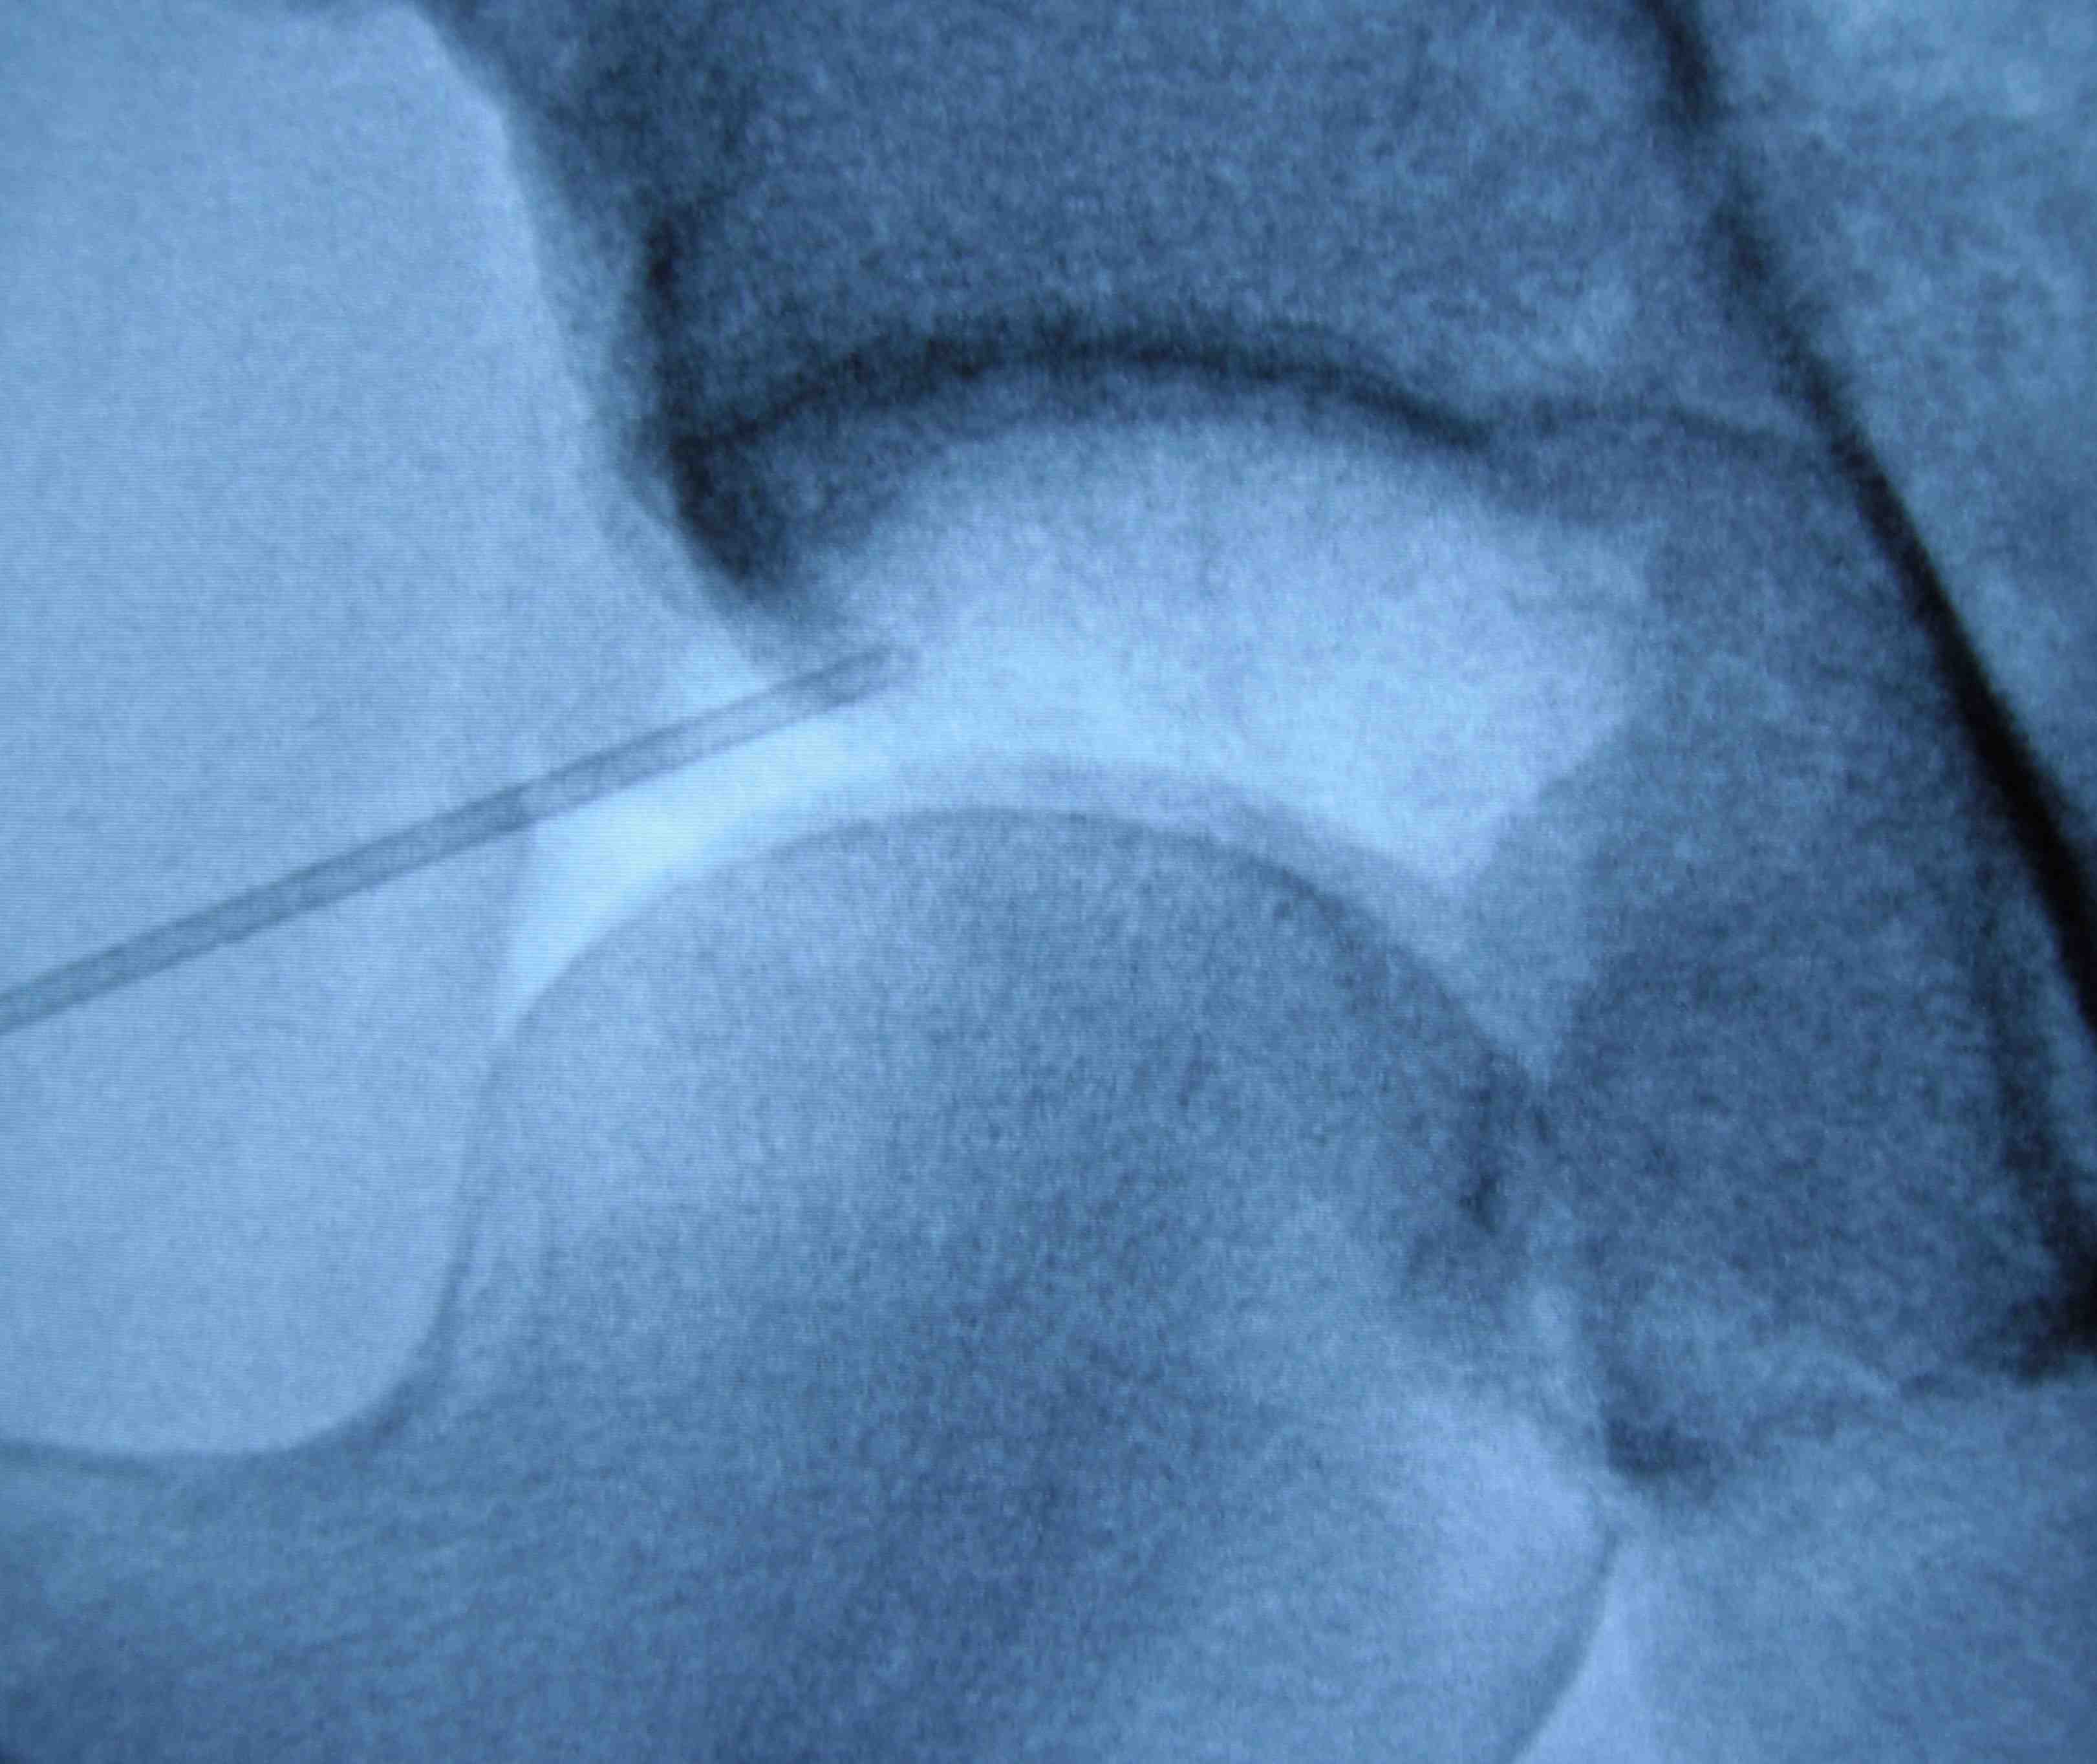

It is important to manage these conditions initially with good physiotherapy and core exercises. Intra-articular injections of cortisone are often used, but seldom provide long term relief. They can however be useful to determine if the pain is coming from the labral tear, or from another source.

During this keyhole procedure, anchors with sutures are used to repair the labral tear. Extra bone is taken away from the acetabulum and the femoral head / neck area as needed. Usually the hip capsule is opened to access the hip joint fully, and this is carefully closed at the end of surgery.